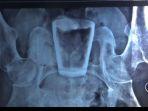

Ada Gelas Kaca dalam Tubuh Pria di Jember, Dokter Menduga Dimasukkan Lewat Anus

Ada gelas kaca di dalam tubuh seorang pria di Jember ini. Dokter menduga gelas tersebut dimasukkan dari anus.

FAKTA Gelas Kaca Ditemukan Dalam Perut Pria di Jember: Sakit Selama 3 Bulan, Dokter Beri Penjelasan

Sebuah gelas kaca ditemukan dalam perut pria di Jember, Jawa Timur. Nur Lasiadi (33) harus menjalani operasi untuk mengeluarkan benda asing itu.

Pria Jember Merasa Sakit di Bagian Ulu Hati, Ternyata Ada Gelas Kaca dalam Perutnya

Selama 2 jam, tim medis RSD Balung melakukan operasi mengeluarkan gelas itu pada 29 Maret 2022 dan diketahui posisi gelas di bagian rectum atau anus